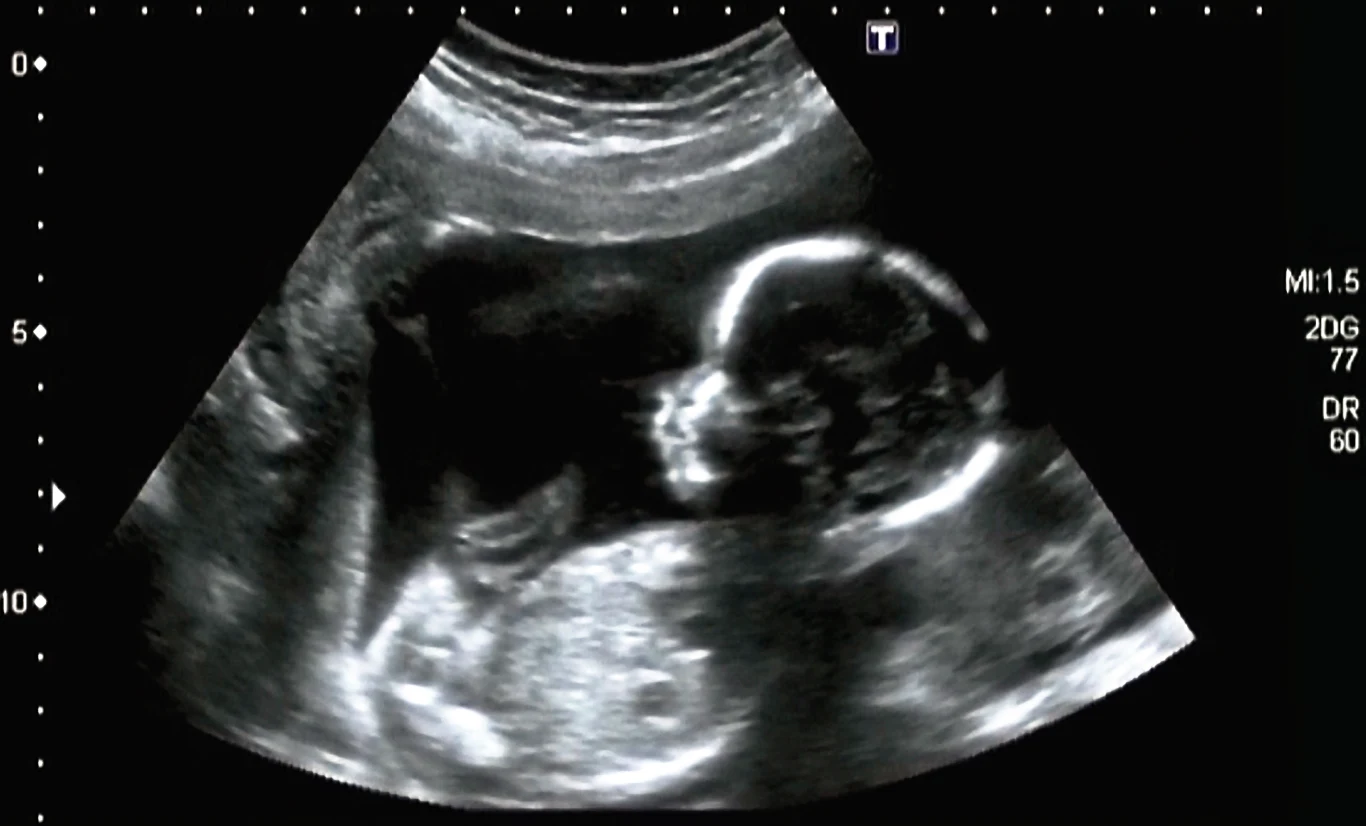

Płód w płodzie

Na początku marca lekarze z Fudan University w Szanghaju podzielili się wynikami badań, w których opisali przypadek rocznej pacjentki z wyraźnie powiększoną głową i problemami z motoryką. Tomografia komputerowa wykazała znaczne ściśnięcie mózgu i nagromadzenie w jego komorach płynu, więc podjęli decyzję o operacji, by ratować zdrowie i życie dziewczynki. W jej trakcie okazało się, że dziewczynka cierpi z powodu tzw. fetus in fetu, czyli płodu w płodzie - to rzadka anomalia, która powstaje podczas bardzo wczesnych stadiów ciąży bliźniaczej wskutek nierównomiernego rozdziału totipotencjalnych komórek blastocysty, rezultatem czego jest otoczenie jednego z zarodków przez drugi. Mówiąc wprost, wewnątrz mózgu pacjentki znajdował się płód jej nienarodzonego bliźniaka. Szokujące? I tak, i nie. Bo chociaż nie jest to przypadłość nieznana medycynie, to wyjęcie z mózgu rocznego dziecka nierozwiniętej masy płodowej z wykształconymi kończynami górnymi, na których widoczne są nawet wypustki przypominające palce, nie jest przypadkiem, z jakim lekarze mierzą się na co dzień.